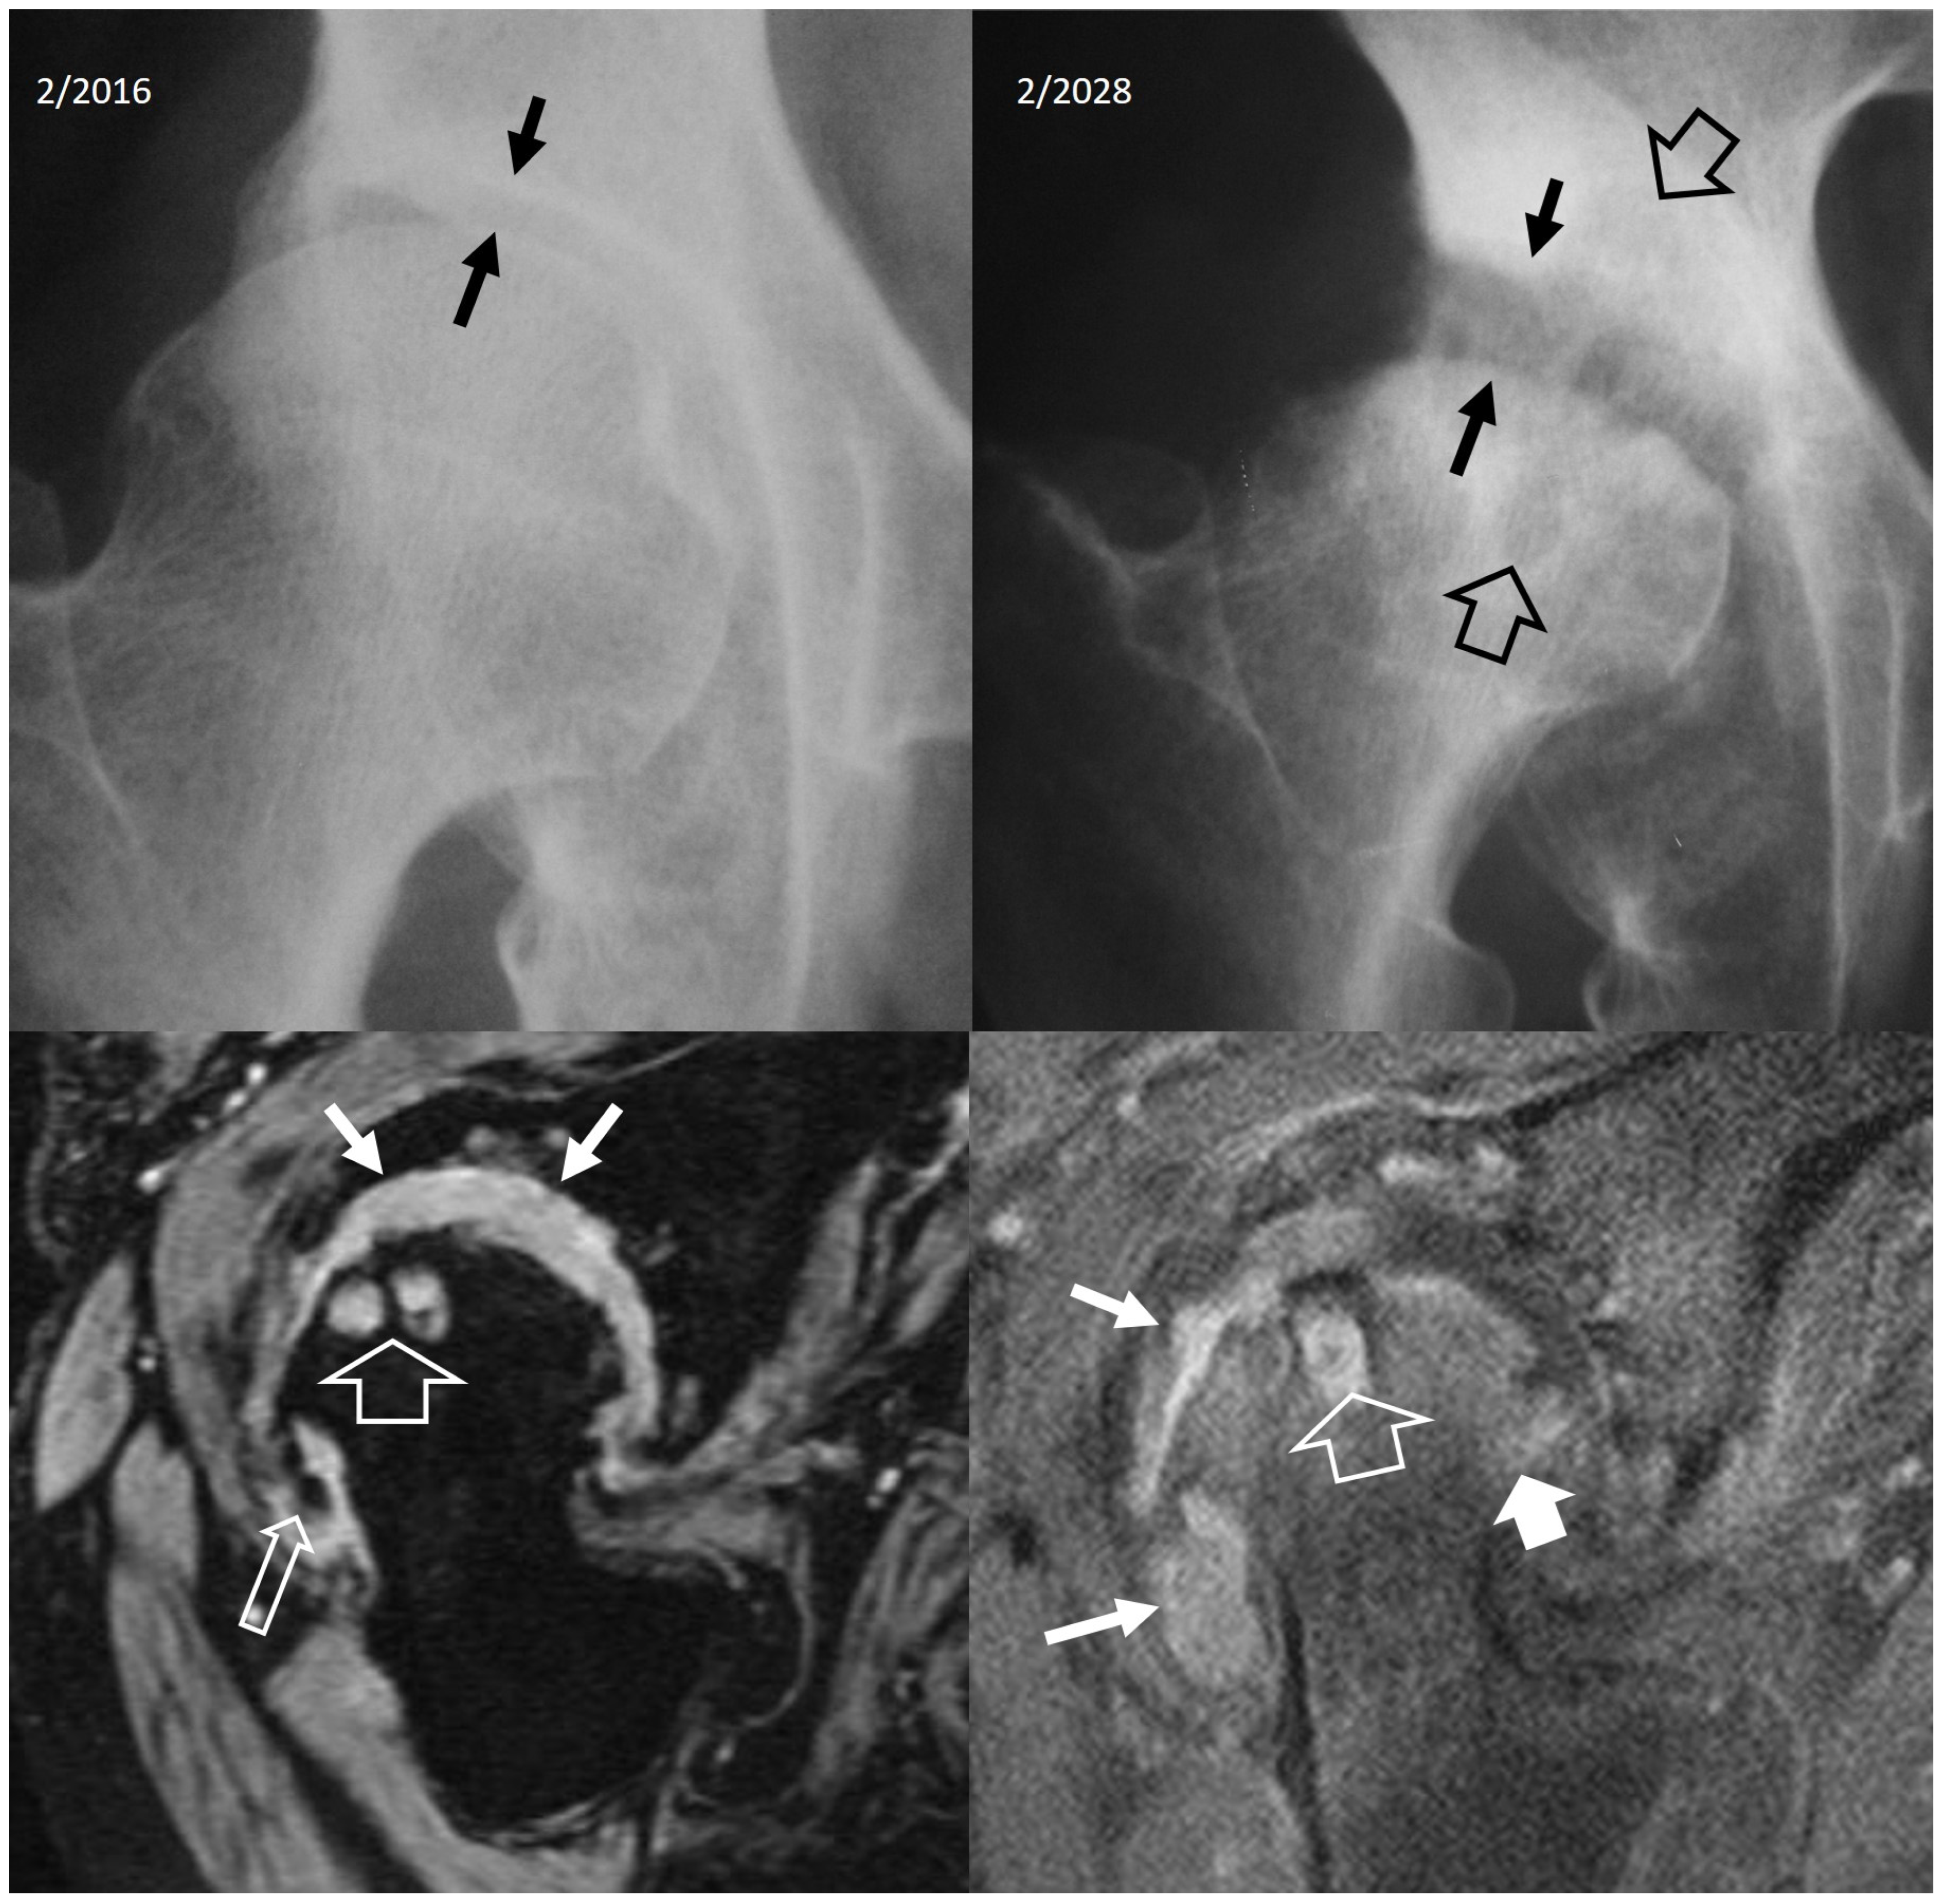

4.2.4. Rapidly Destructive Osteoarthritis of the Hip

- Flemming, D.J.; Gustas-French, C.N. Rapidly progressive osteoarthritis: A Review of the clinical and radiologic presentation. Curr. Rheumatol. Rep. 2017, 19, 42. [Google Scholar] [CrossRef] [PubMed]

- Boutry, N.; Paul, C.; Leroy, X.; Fredoux, D.; Migaud, H.; Cotton, A. Rapidly destructive osteoarthritis of the hip: MR imaging findings. AJR Am. J. Roentgenol. 2002, 179, 657–663. [Google Scholar] [CrossRef] [PubMed]

- Zazgyva, A.; Gurzu, S.; Gergely, I.; Jung, I.; Roman, C.O.; Pop, T.S. Clinico-radiological diagnosis and grading of rapidly progressive osteoarthritis of the hip. Medicine 2017, 96, e6395. [Google Scholar] [CrossRef] [PubMed]